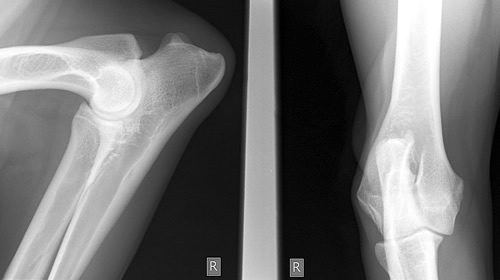

MESTRE – Nell’ospedale all’Angelo di Mestre è stato eseguito un intervento definito dai medici “ai confini della chirurgia ortopedica”. Un paziente di 55 anni aveva un’ossificazione al gomito a causa di un infarto con ipossia cerebrale. L’articolazione del braccio risultava inesistente perché al suo posto si era creato un unico blocco solidificato grosso quanto un limone. L’uomo era limitato nei movimenti a causa dell’infarto e non era più in grado di muovere il braccio che rimaneva bloccato nella posizione flessa.

L’intervento è stato eseguito dal dottor Andrea Miti, primario di Ortopedia, che spiega le ragioni dell’intervento: “Esisteva un’unica soluzione: aprire l’arto e togliere tutta l’articolazione trasformata in ossificazione, asportando anche le parti terminali dell’omero e dell’ulna, sopra e sotto l’articolazione del gomito”. Il primario ha quindi asportato dal braccio tutto il blocco osseo formatosi sull’articolazione e le parti finali di omero e ulna che erano rimaste cementate. Il dottor Miti ha spiegato che al posto della parte asportata era necessario inserire una protesi già composta delle sue parti. “Abbiamo realizzato queste parti terminali utilizzando le ossa necessarie prelevate da cadavere – ha raccontato il primario – le abbiamo rese adatte al trapianto, abbiamo inserito tra le due ossa l’articolazione protesica in titanio”.